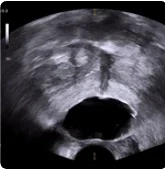

169 cc prostate ultrasound saggital view showing BioProtect Balloon Spacer, prostate, and rectum.

Saggital Ultrasound

Image courtesy of of Dr. Vishesh Agarwal, Radiation Oncologist.